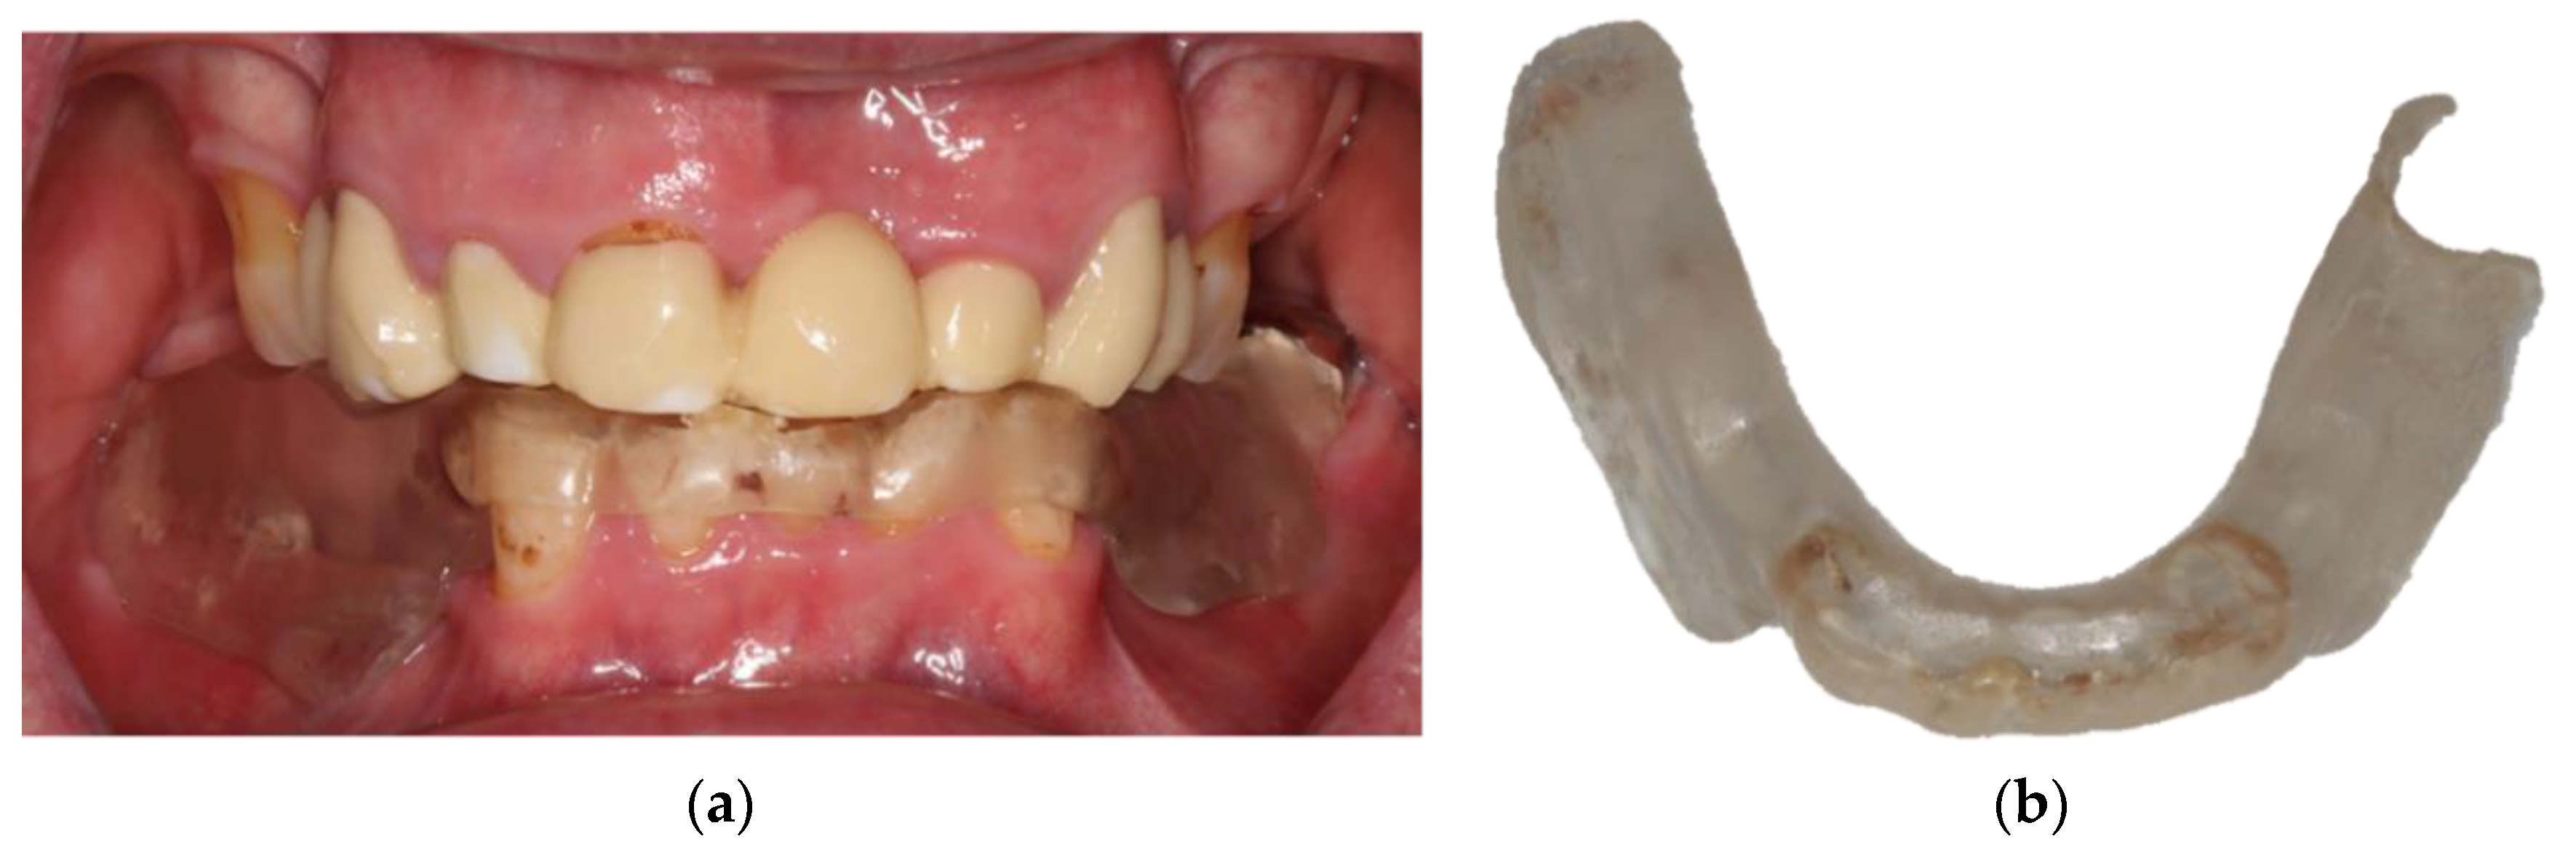

- Locator abutments on both implants, single-crown FDPs on the remaining lower molar teeth, insertion of a tooth-colored and tooth-shaped monolithic RDP fabricated from POM with minimally invasive preparation of the lower anterior teeth (experimental character in long-term endurance).